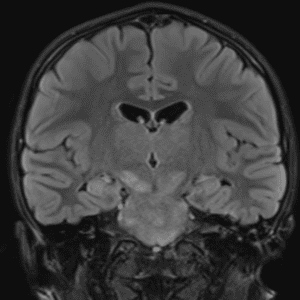

Case #31

Optic pathway glioma